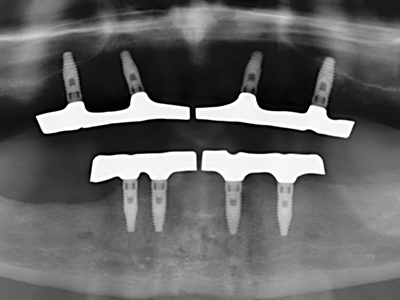

Preparation of the lateral window during an external sinus floor elevation is challenging, particularly for implantologists with little surgical experience. Removal of the bone cover of the sinus without injuring the underlying Schneiderian membrane is only part of the operation – after establishing an adequate access, the membranous lining of the sinus must be carefully mobilized to make space for the augmentation materials or the implants. Piezo surgery is useful for this indication in two ways: diamond-coated instruments can be used for selective bone ablation and the underlying mucous membrane remains intact when the procedure is done carefully. The ultrasonic frequencies also enable detachment of the mucous membrane without complications – the frequencies are transmitted into the space between the mucous membrane and sinus floor by special blunt attachments (Cassetta, Ricci et al. 2012, Pereira, Gealh et al. 2014) (Rickert, Vissink et al. 2013). As a result, it is not surprising that current reviews of external sinus floor elevation positively evaluate the use of piezoelectric devices as well as the use of roughened implant surfaces and bone replacement materials (Wallace, Tarnow et al. 2012).